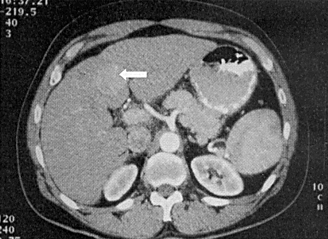

Developing a scoring system for staging patients with hepatic colorectal metastases is important for prognosis and for identifying those who will benefit from additional systemic therapy.

Due to advances in chemotherapy, biologic therapy, and the development of liver-oriented treatment options, the survival of patients with metastatic cancer has more than doubled, and increasing numbers of patients have been cured, even among those with advanced disease.

This article will review the current practice of hepatic resection for colorectal liver metastases, including the possibility of combined resection of hepatic metastases at the time of resection of the primary cancer.